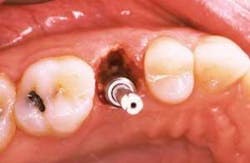

In order to preserve the extraction socket dimensions, immediate implant placement at the time of extraction has been proposed. Briefly described, the technique involves a minimally traumatic extraction of the tooth.

The appropriate implant osteotomy is carried out and the implant is then placed. Typically, the osteotomy will extend beyond the apex of the extraction socket in order to provide primary stability of the implant.

Voids between the implant and the extraction socket walls are filled using a particulate bone graft material (Figures 1 and 2).